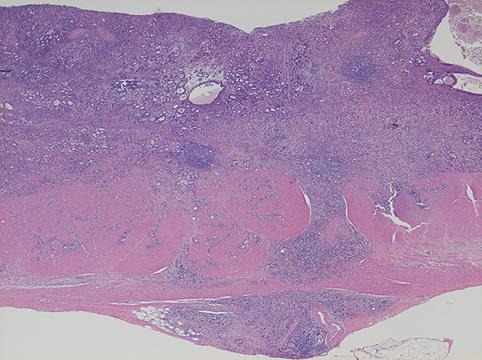

疾患(病理主体)の分類悪性上皮性腫瘍/腺癌

部位(臓器別)胃(部位)/体部

検査方法ミクロ

腫瘍の肉眼分類3型(潰瘍浸潤型)/

病変の最大径(ミリ)30〜34

腫瘍の深達度ss(a1)